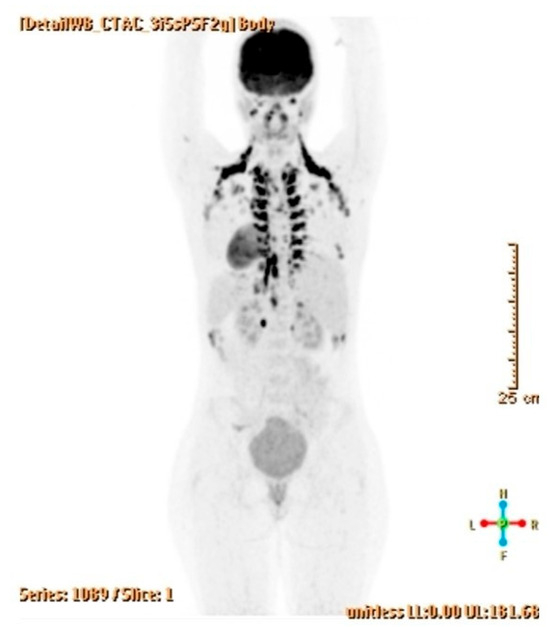

Mature teratomas account for approximately 20% of all ovarian tumors identified in pathological studies. Benign or malignant somatic neoplasms developing within teratomas can arise from any tissue in up to 2% of mature cystic teratomas, including low-grade malignant mucinous neoplasms. This report presents [...] Read more.

Mature teratomas account for approximately 20% of all ovarian tumors identified in pathological studies. Benign or malignant somatic neoplasms developing within teratomas can arise from any tissue in up to 2% of mature cystic teratomas, including low-grade malignant mucinous neoplasms. This report presents the case of a 34-year-old woman with no previous gynecological or general health issues, who was admitted to our Hospital after an asymptomatic pelvic mass was detected during a routine exam. A transvaginal ultrasound revealed a unilateral pelvic mass in the left adnexal region, measuring 8 cm. The CT scan showed a cystic-appearing formation measuring nearly 12 cm, which indented the bladder dome. Final diagnosis indicated a mucinous carcinoma arising from a mucinous borderline lesion within the context of a mature ovarian teratoma. No other involvement or lymphadenopathies were detected on 18FDG-PET CT scan, and the patient is now well and free of recurrences. Full article

(This article belongs to the Special Issue Pathology and Diagnosis of Gynecologic Diseases, 3rd Edition)